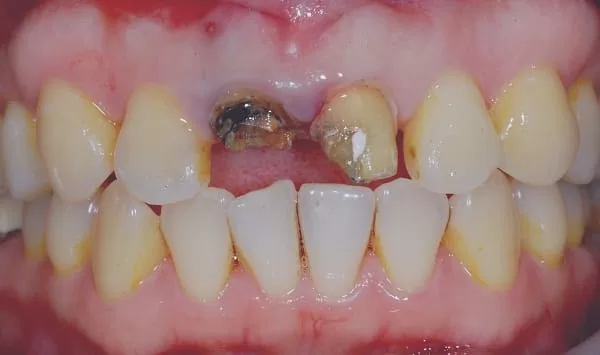

拆除原來牙套及釘子,拔牙後看到牙根確實斷裂 ~~~ ε(┬┬_┬┬)3 心痛!

當天立即植牙,外側約5x7mm的骨缺損。缺損處醫師早再事前已經告訴我要實施 骨再生手術,充填骨粉後使用再生膜覆蓋並縫合傷口。治療後醫師讓我看手術中拍攝的照片,順便解說治療步驟,照片好嚇人喔!